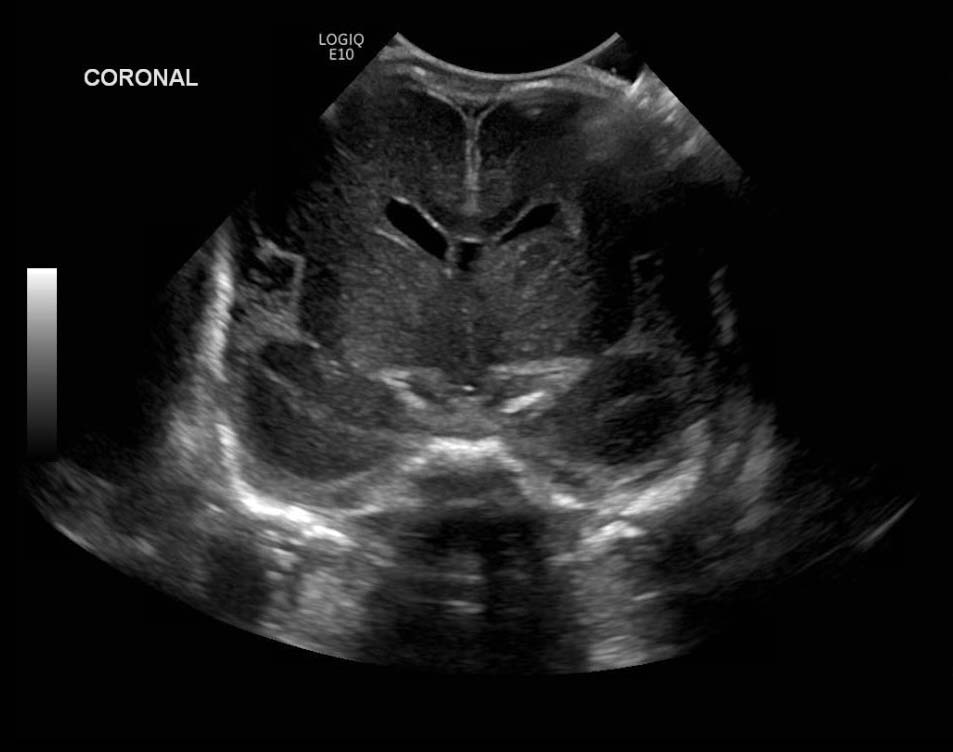

Age: 4 days (born at 24 weeks)

Sex: Male

Indication: Evaluate for germinal matrix hemorrhage

Grade 2 germinal matrix hemorrhage

Sample ReportLeft germinal matrix hemorrhage involving the caudothalamic groove and layering in the occipital horn of the left lateral ventricle without hydrocephalus (grade 2).

No abnormal brain parenchymal echogenicity or extra-axial collections.

Premature sulcation pattern.